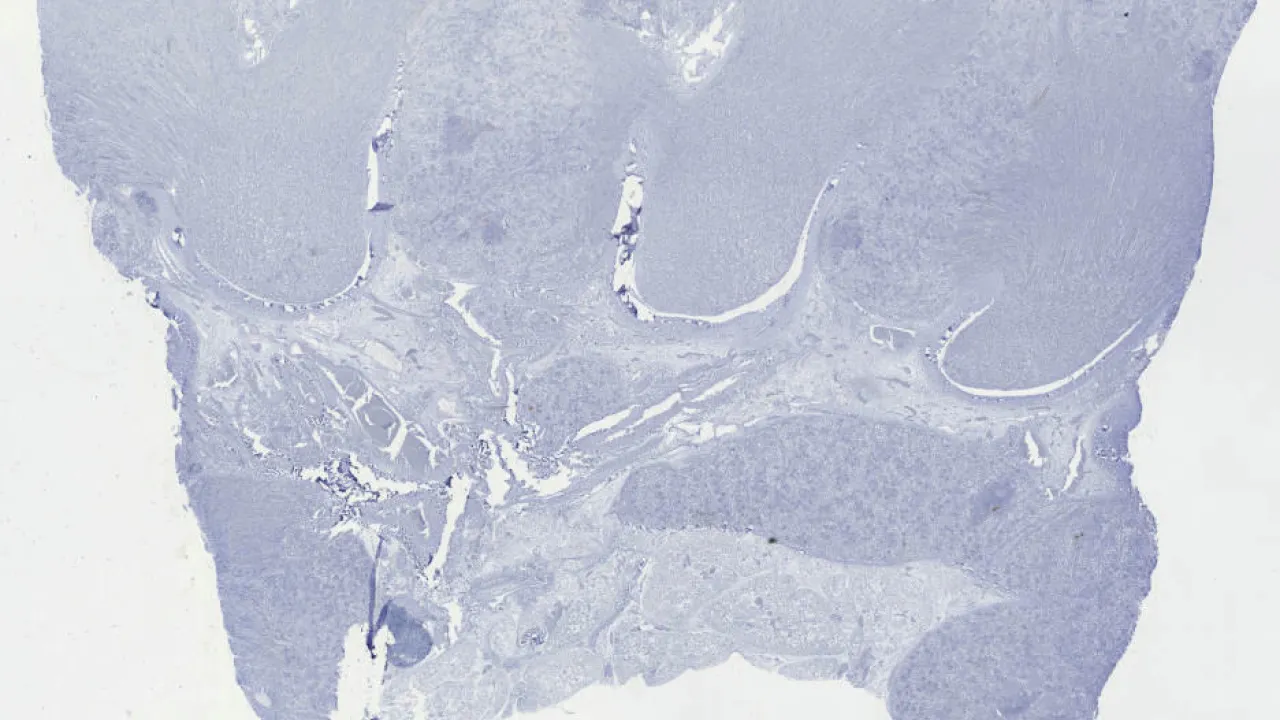

Kidney, Xanthogranulomatous pyelonephritis, Trichrome stain